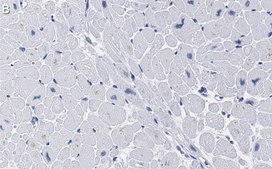

Immunohistochemistry (Paraffin) Analysis: A 1:100 dilution from a representative lot detected SDHB in human kidney and human heart tissue sections.